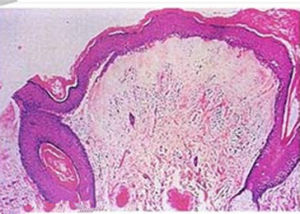

根據患者有外陰瘙癢及典型好發部位、臨床表現,局部色素脫失且呈白色斑片,病理檢查有角化過度,棘細胞層萎縮,真皮水腫和膠原纖維變性,可作出診斷。